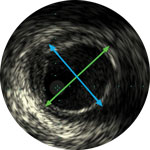

Der digitale IVUS Visions PV.014 Rx wurde für die Beurteilung von pAVK-Läsionen entwickelt. Er ist 55 % steifer als der Eagle Eye Platinum Coronary IVUS12 und verfügt über ein 20 mm großes Sichtfeld in einem 5F-kompatiblen Katheter.

Der digitale IVUS Visions PV.018 verfügt über ein 24 mm großes Sichtfeld in einem 6F-kompatiblen Katheter und dient zur Beurteilung von Gefäßstruktur und -pathologie. Er erleichtert die Festlegung von Behandlungsalgorithmen und ermöglicht bessere endovaskuläre Ergebnisse.13